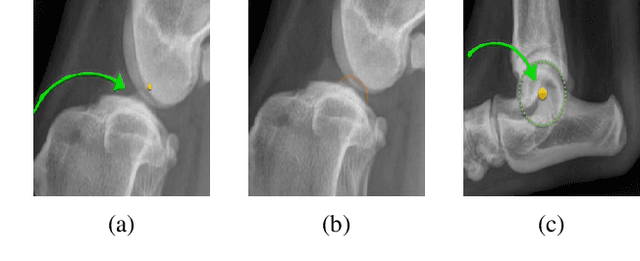

Abstract:Stifle joint issues are a major cause of lameness in dogs and it can be a significant marker for various forms of diseases or injuries. A known Tibial Plateau Angle (TPA) helps in the reduction of the diagnosis time of the cause. With the state of the art object detection algorithm YOLO, and its variants, this paper delves into identifying joints, their centroids and other regions of interest to draw multiple line axes and finally calculating the TPA. The methods investigated predicts successfully the TPA within the normal range for 80 percent of the images.